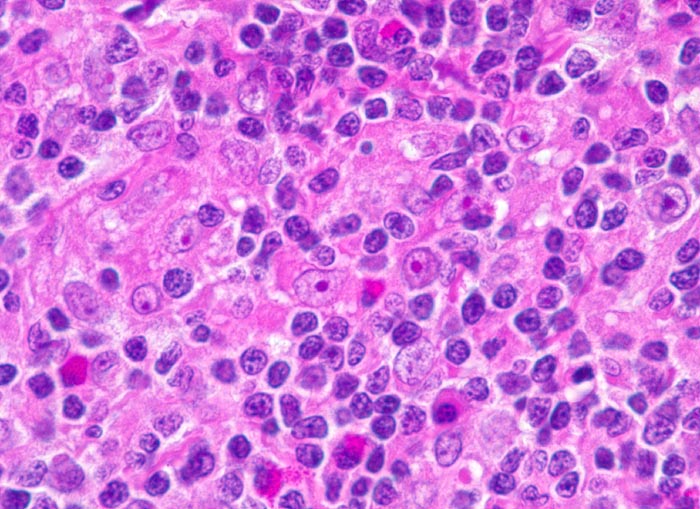

PathoPic – image database / PathoPic ID 3875 - Hodgkin-Lymphom, Mischzelltyp: Hodgkin Zellen

Hodgkin-Lymphom, Mischzelltyp: Hodgkin Zellen

Nachweis von Hodgkin-Zellen: grosse, blastoide Zellen mit grossem Kern und grossem eosinophilen Nukleolus. Ansonsten gemischtzelliges Infiltrat aus reaktiven Zellen: Lymphozyten, Histiozyten, Plasmazellen und eosinophilen Granulozyten.

Vergrösserte zervikale und axilläre Lymphknoten, Fieber und Nachtschweiss.

Histologie

630